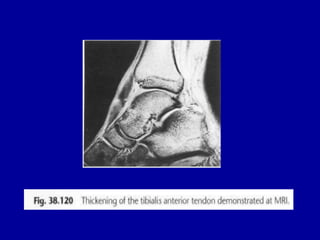

• 130.